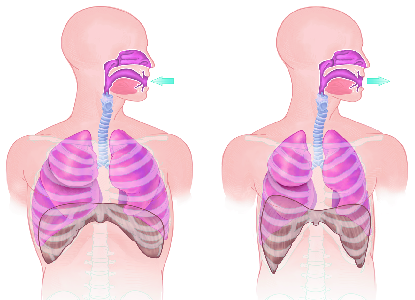

Detailreiche Fotografien aus der medizinischen Praxis ergänzen die Texte; moderne, genaue,

wissenschaftliche Zeichnungen geben Einblick in die Anatomie und die Funktion der Lunge und

anderer Organe.